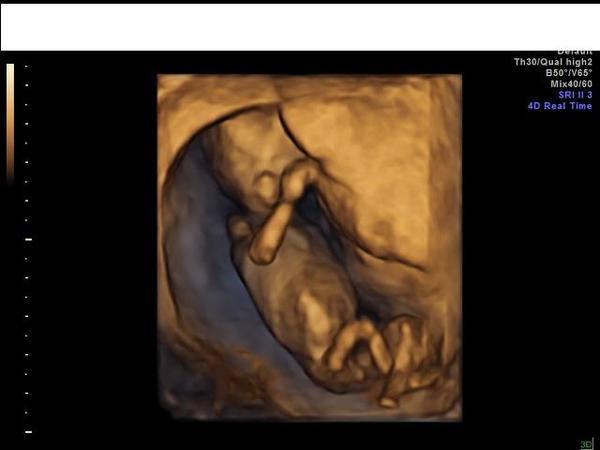

dle CRL jsem byla ve 14+1 na NT screeningu. Když jsem se ptala, co že to vidím mezi nožičkama, tak mi doktorka řekla, že pohlaví říct s jistotou nemůže, že to může být pindík nebo klitoris. Ale když se dívám na fotku, tak si prostě nedokážu představit, že je to holčička. 😀 A i když jsem po příbuzných nic neříkala, tak všichni říkali hend jééé chlapeček. Tak se schválně chci zeptat jestli měl někdo taky takové fotky a byla to nakonec holčička. 🙂

Přikládám foto:

já jsem se takhle podívala na svůj ultrazvuk z NT screeningu a viděla jsem kluka (a to nebyl 3D) a teď mi tu běhá 2 letý Honzík. Na tvé fotce taky vidím chlapečka, ale u kamarádky jsem se netrefila. Viděla jsem kluka a je to Kristýnka 🙂

Ja tam tedy nic nevidim ☹

Urcite nevidim pindoura. Spiseto je snura, stin, nevim.